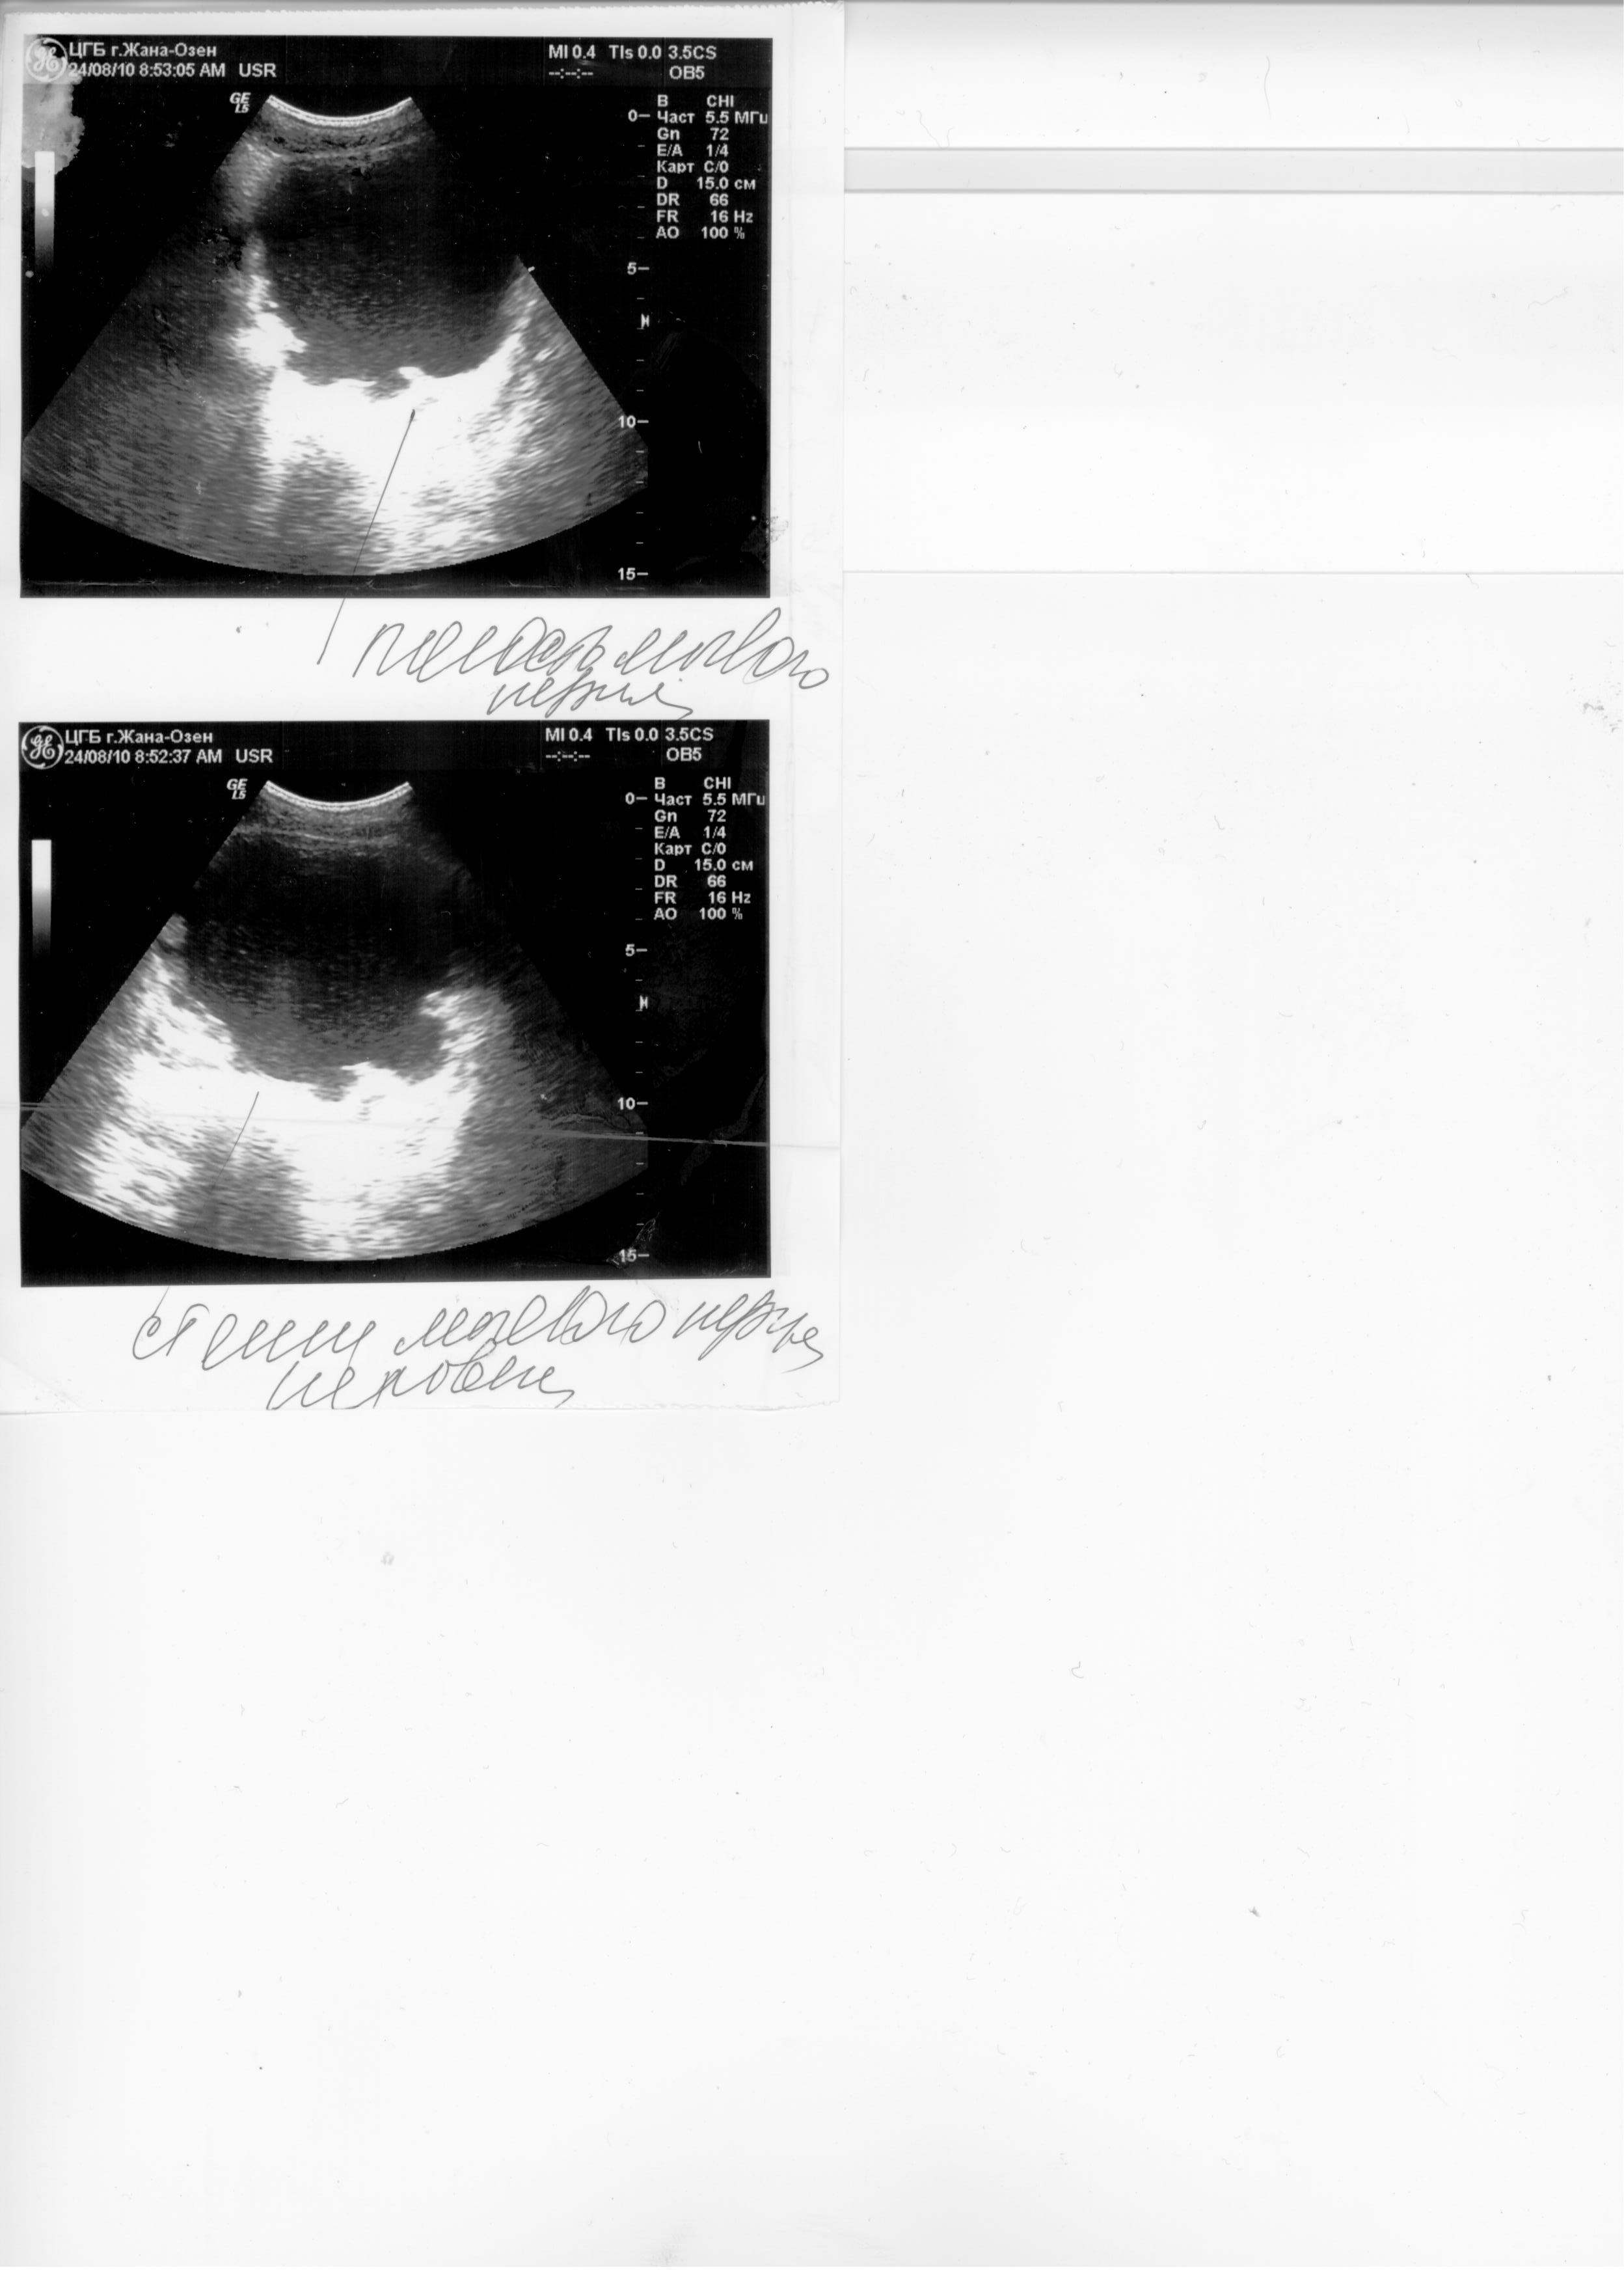

Здравствуйте. Травма С5 в 2003 г. Разница между обследованием 2, 2.1, 2.2 и 1, 1.1, 1.2 одна неделя. Остаточная моча 500-600мм. Уролог сказал, что надо ставить эпицистому, лечащий врач нейрохирург посоветовал не спешить, поставить катетер фолея на дней 10 опорожняя мочевой через каждые 5-6часов. У меня хр. цистит, хр. пиелонефрит. Посоветуйте пожалуйста что делать в данной ситуации? С уважением Руслан.